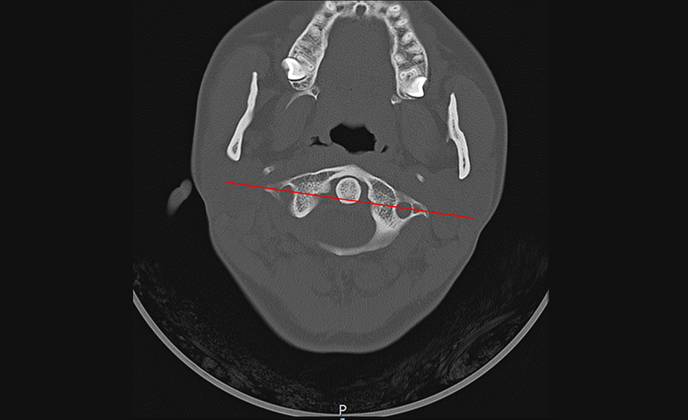

체형교정, 족부교정, 턱관절교정, 턱관절 난치성 질환, 근골격계통증, 척추관절질환, 추나요법, 약침, 한방내과

척추관절질환, 교통사고후유증, 턱관절난치병, 화병, 소화기질환, 안면마비